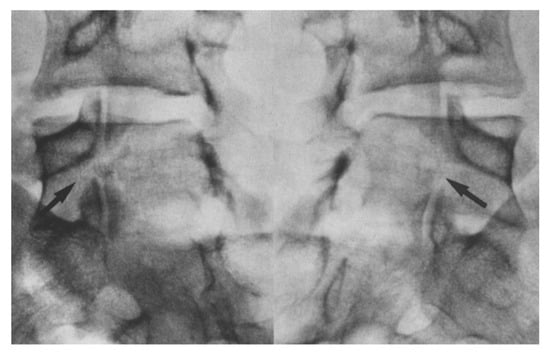

1.5. Imaging